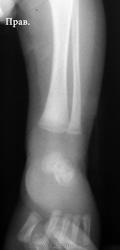

В проксимальных метафизах большеберцовых - такие же полоски.

Давно не встречалась с врожденным костным сифилисом, лет 10, позабылось все (раньше, в другой больнице, видела его достаточно часто), но что могу сказать - полосы просветления в метафизах (а также полосатость ядер окостенения пяточной и таранной костей) встречаются не только при сифилисе, часто видела их у здоровых недоношенных;  при сифилисе, кроме этих полос, должно быть расширение и зазубренность зон предварительного обызвествления, симметрично в костях голеней и предплечий, клинически, обычно, не проявляется, только при третьей стадии остеохондрита, когда появляются псевдопараличи Парро - появляется припухлость, отек, ограничение движений, и это также с обеих сторон. Здесь мне видится нечеткость метафиза малоберцовой кости слева, скорее всего, обычный остеомиелит. Конечно, анализ на сифилис, все-равно, заказать надо.